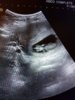

Både gleder og gruer meg, blir jo et tungt svangerskap en tung tid de første månedene, men når veien har vært så lang så er det jo en ekstra bonus! Det er jo fantastisk at du også fikk det til!Forøvrig litt sjalu på dere tvillinggravide.. Misunner skikkelig de på termingruppen min som har to i magen selv om jeg vet at frøkna blir verdens mest bortskjemte og etterlengtede frøken [emoji173]️